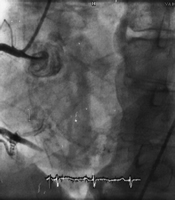

一例63岁男性因“气促”入院。既往有高血压、卒中和酒精滥用史。入院时心率120次/分,颈静脉充盈,第一、第二心音规则,胸骨左缘可闻及Ⅲ~Ⅳ级全收缩期杂音,吸气时增强。超声心动图提示弥漫性左室运动功能减退,室间隔远端节段性无运动。LVEF为30%。心导管检查未显示冠脉闭塞,而发现在RCA和右室之间存在一处2 mm长的瘘道(如图)。